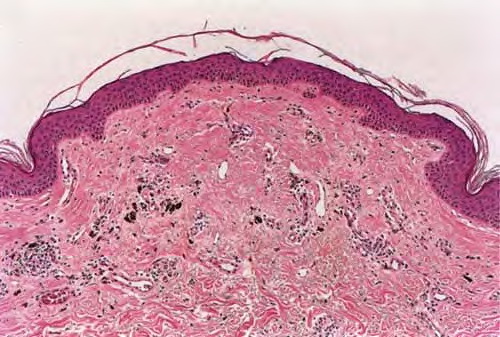

Regressing melanoma = الميلانوما المتراجعة